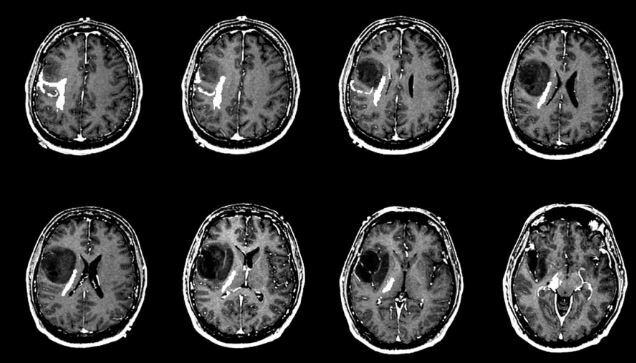

وی سرطان مغز را یکی از کشندهترین انواع سرطانها توصیف کرد که میزان بقای آن نسبت به انواع دیگر سرطانها کمتر است و اظهار کرد: تشخیص زود هنگام میتواند در درمان موثر باشد. روشهای تشخیصی که در حال حاضر برای تشخیص سرطان مغز استفاده میشود خیلی دقیق نیستند و مطمئنترین روش تشخیص دقیق سرطان مغز، بیوپسی است.

این محقق گفت: همچنین به دلیل تشابه ظاهری بافت سالم و سرطانی، تشخیص برای جراح در حین عمل مشکل است، لذا برداشتن ناقص تومور و یا برداشتن بافت سالم میتواند بر سلامت فرد تاثیر بگذارد؛ بنابراین استفاده از روش تشخیصی دقیق و زودهنگام برای تومور مغزی بسیار مهم خواهد بود.

این دانشآموخته دانشگاه امیرکبیر با اشاره به دیگر نتایج به دست آمده از این مطالعات گفت: ما در این تحقیق مشاهده کردیم که تفاوتهای قابل توجهی بین انتشار پلاسمایی بافت سالم و گلیومهای مغزی است به گونهای بررسیهای ما نشان داد تفاوت بافت سالم و ناسالم مغز در شدت عناصر است و اختلافات واضحی بین شدت نسبی عناصری، چون "باریم"، "کلسیم"، "منیزیم"، "فسفر"، "منگنز" و "آهن" در بافت سالم و سرطانی وجود دارد. در بافت سرطانی مقدار این عناصر نسبت به بافت سالم بیشتر است.